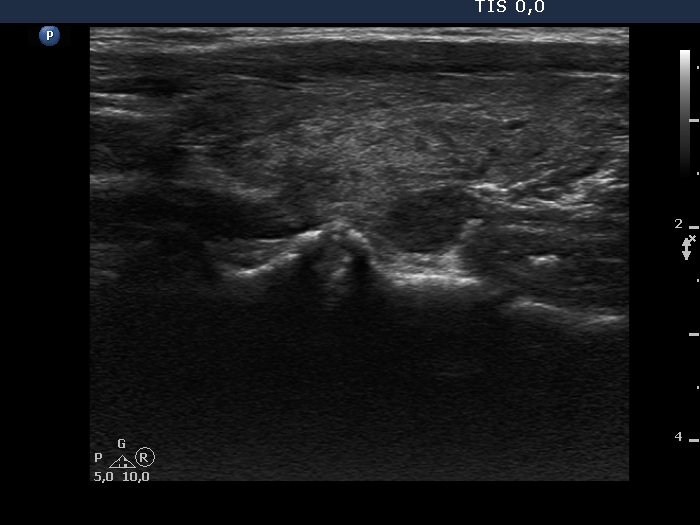

100 consecutive cases of papillary cancer - case 088 (ultrasonographic picture 9)

Right lobe, longitudinal scan